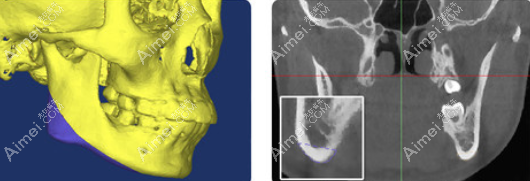

2、何锦泉医生可做3D导板正颌手术:

何锦泉的3D导板正颌术可以精细到0.1mm,所以做正颌手术截骨的时候量把握非常准,而且还能够避开重要的血管和神经,减少创伤,有利于术后的恢复。